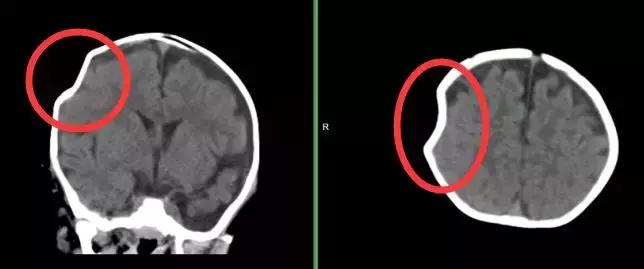

爷爷骑摩托车载着妈妈和仅7个月大的菲菲(化名)出行,结果飞来横祸,一辆货车迎面撞向摩托,爷爷当场死亡,菲菲被卷入车底昏迷不醒,且头部血流不止。紧急送至当地县医院后,通过CT检查医生发现菲菲颅内出血、枕骨骨折。因当地医疗条件有限,医生建议患者转至擅长脑外伤治疗的福建三博福能脑科医院作进一步诊治。3月18日,我院神经外科专家张金锋主任为菲菲进行了血肿清除术,术后第二天孩子便清醒了,目前正在进一步康复治疗中。

术前孩子颅脑出血

术后血块消失